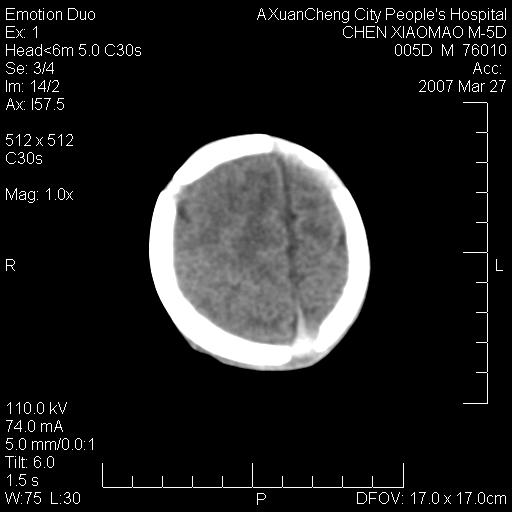

大家看看可有出血?另外枕骨中央是骨缝还是骨折

缝是正常的,但患儿有hie

大家看看可有hie ?还有左侧枕部胡形高密度ct为45~53hu,可有硬膜下血肿?

左颞枕部有出血,枕骨有骨折

枕骨骨折可以下,应该比较明显,颅内还是正常的,不放心的话,短期随访。

未见明显异常,,那是横窦影,“缝”是后囟